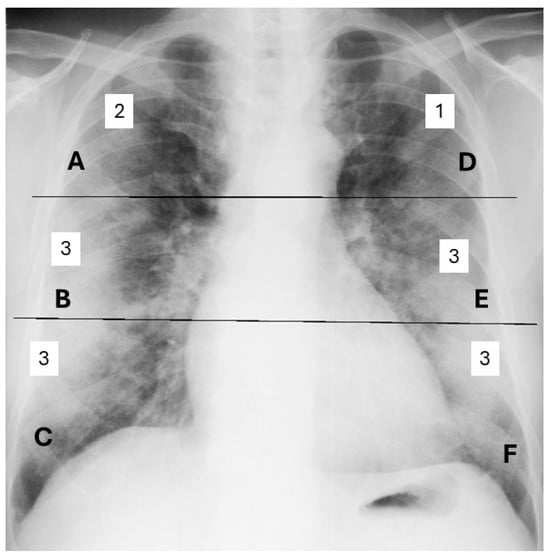

| Anatomy Region | Score | Score 3 | Score 2 | Score 1 | Score 0 | ||||

|---|---|---|---|---|---|---|---|---|---|

| Average ± SD | n | % | n | % | n | % | n | % | |

| A | 0.45 ± 0.84 | 22 | 5.79% | 22 | 5.79% | 63 | 16.58% | 273 | 71.84% |

| B | 0.88 ± 0.80 | 16 | 4.21% | 55 | 14.47% | 180 | 47.63% | 129 | 33.95% |

| C | 1.26 ± 0.85 | 33 | 8.68% | 105 | 37.63% | 173 | 45.53% | 69 | 18.68% |

| D | 0.37 ± 0.75 | 14 | 3.68% | 21 | 5.52% | 58 | 15.26% | 278 | 75.53% |

| E | 0.86 ± 0.76 | 12 | 3.15% | 52 | 13.68% | 188 | 49.47 | 128 | 33.68% |

| F | 1.30 ± 0.86 | 31 | 8.15% | 124 | 32.63% | 156 | 41.05% | 69 | 18.16% |